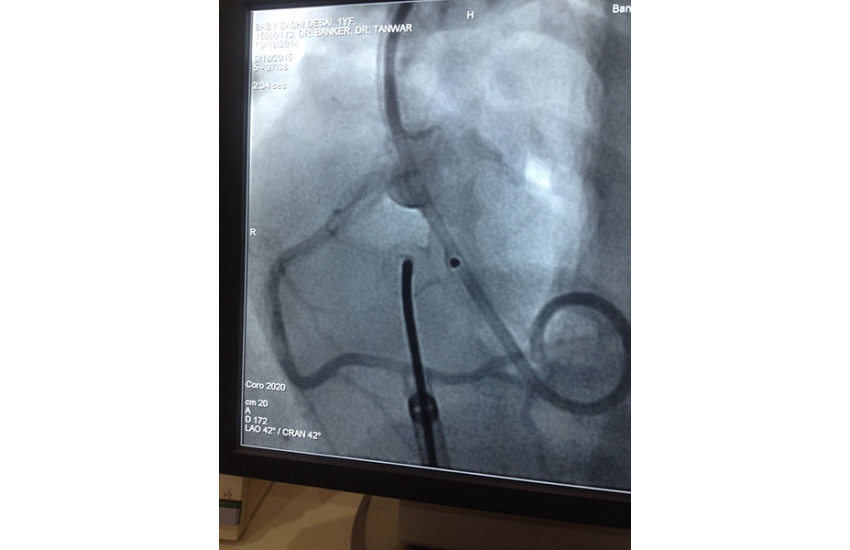

1 year girl with 7 kg weight successfully undergone Ventricular Septal Defect device closure.